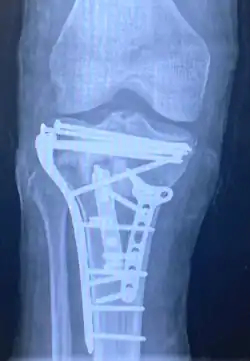

![]() | |

| A severe tibial plateau fracture with an associated fibular head fracture | |

Surgery

A tibial plateau fracture requires orthopaedic surgical intervention for treatment. After X-ray and CT scans confirm fracture, Open Reduction Internal Fixation (ORIF) with medial and/or lateral plateau fixation is done. There are 5 different approaches that are most commonly used.[3]